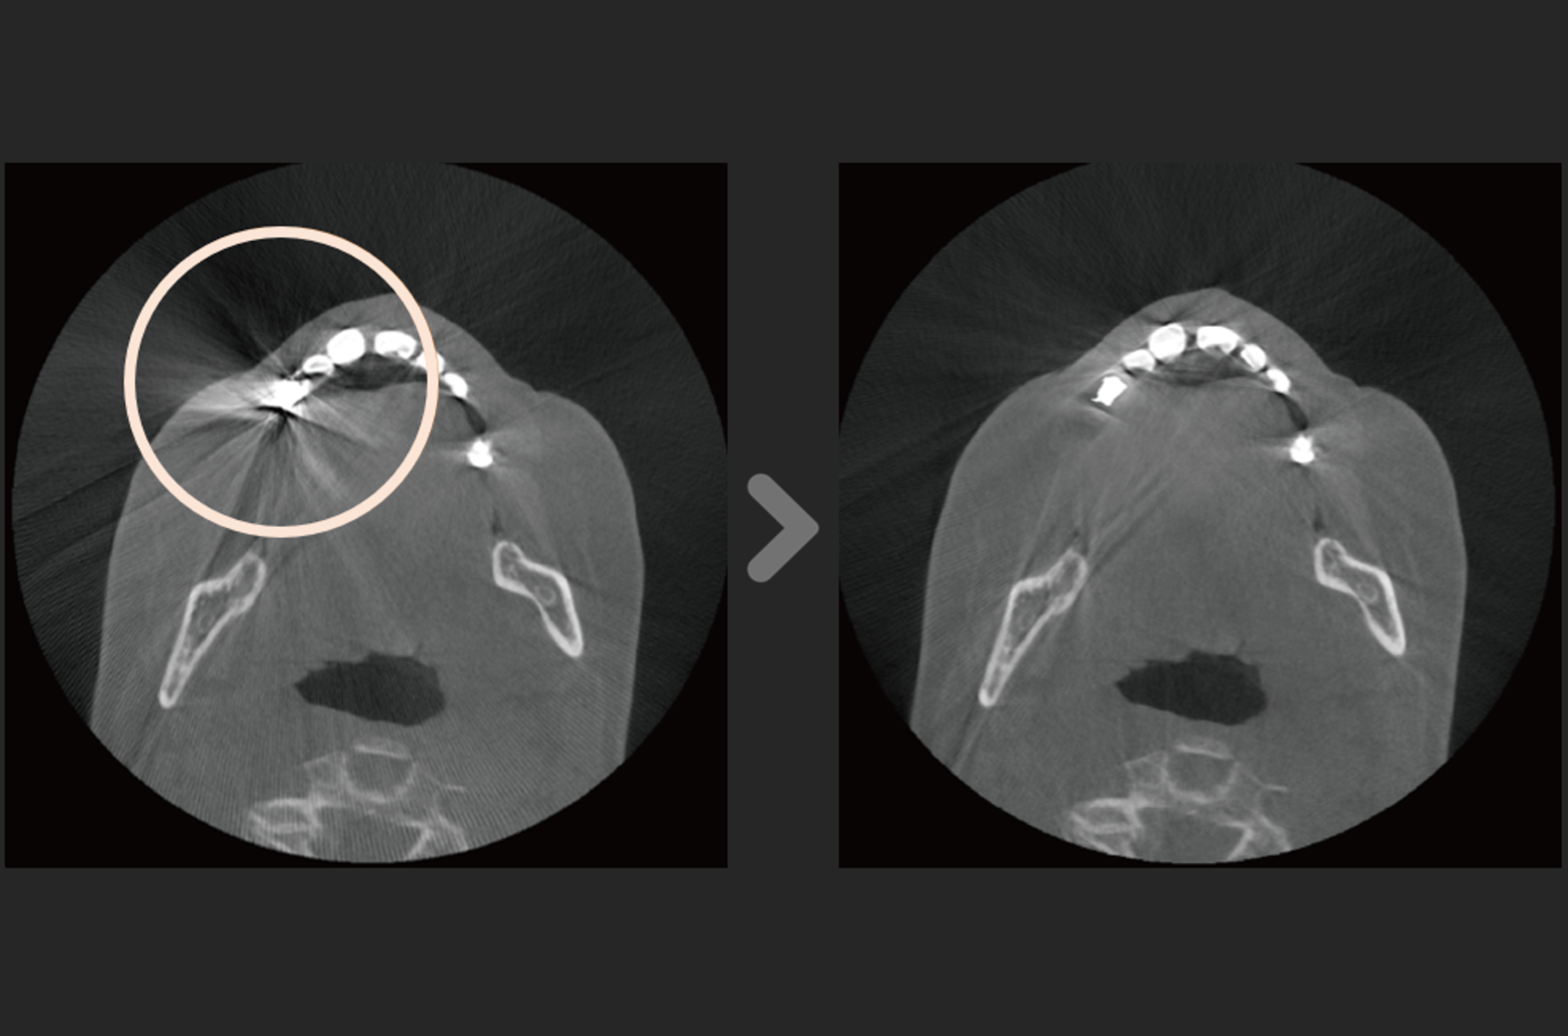

DentiqRecon

3D CT Reconstruction Software